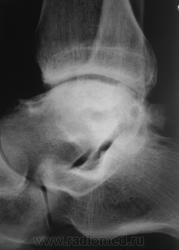

Пациент направлен на рентгенографию голеностопного сустава с диагнозом ДОА.

Травма была два года тому.

Похоже  на  остеохондропатию  блока  таранной  кости  +   ДОА.

А присутствует линейный (или лентовидный, я их путаю) остеопороз, а это признак острого процесса.

С учётом стрелочек, надо полагать, остеомиелит!..

Будем думать, что некроз блока таранной кости не такой уж и асептический, какая-то инхвекция там есть.

Посттравматический артроз с кистовидной перестройкойлатерального мыщелка Субхондральное уплотнение исужение суст. щелей естьИ неконгруэнтность большеберцового эпифиза к таранной маленько просматривается?